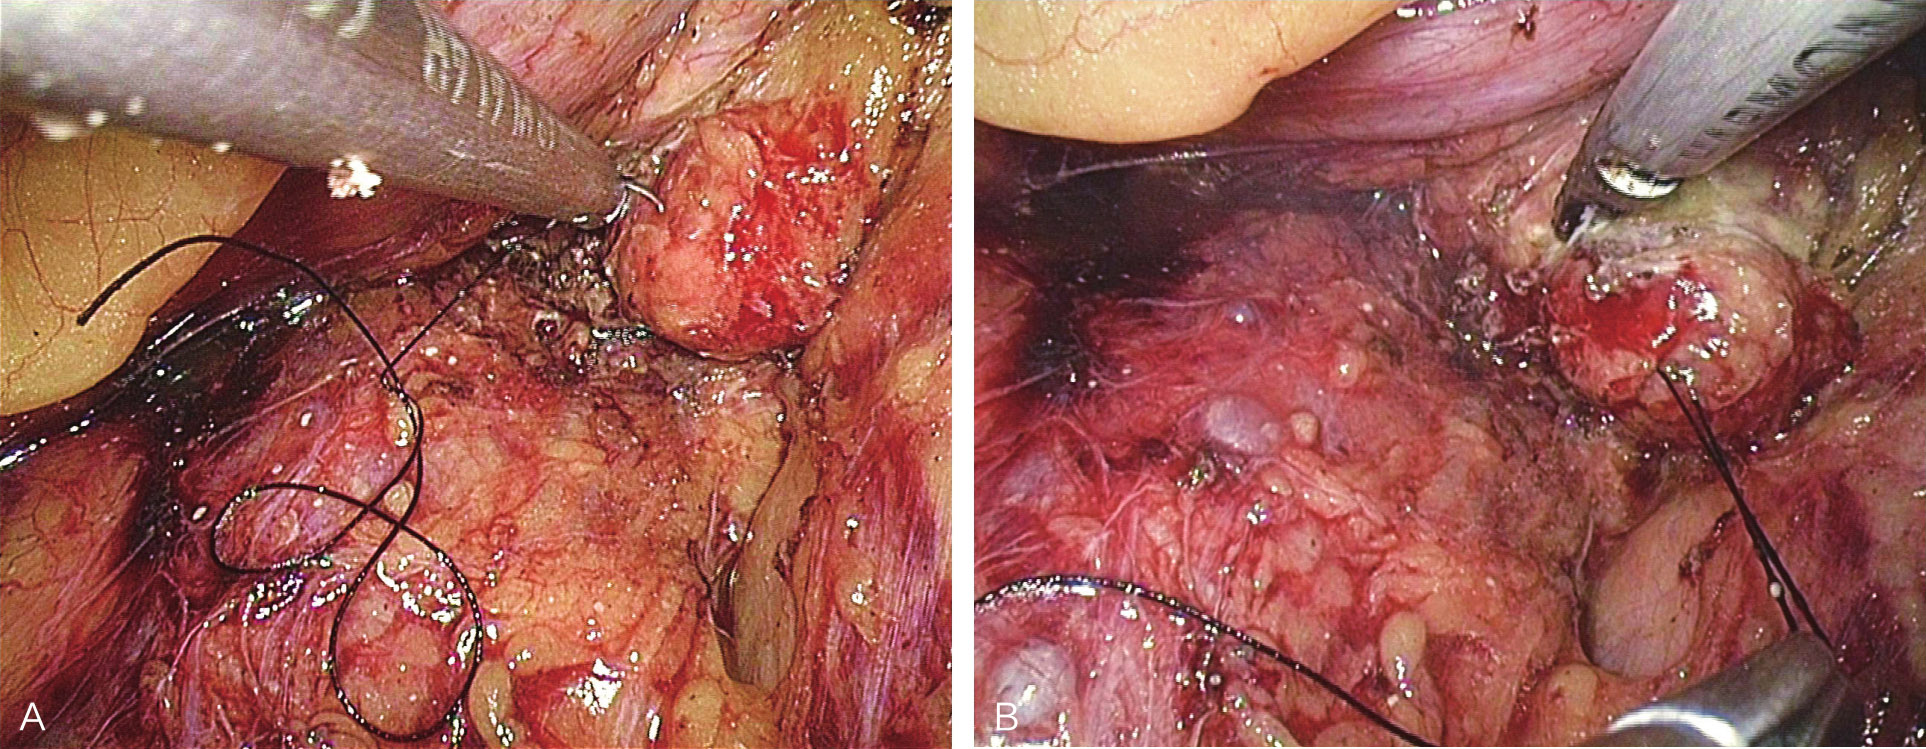

小网膜囊入路腹腔镜胰腺肿瘤剜除术

患者取平卧位,头高脚低,取三孔或四孔法操作;镜下自胃小弯侧网膜弓上方横行打开小网膜囊,探查胰颈,术中定位肿瘤(图6-11、图6-12);镜下缝合肿瘤一针,超声刀完整剜除肿瘤,处理创面(图6-13);取出标本,送冰冻,留置引流(图6-14、图6-15),缝闭切口,术毕。

图6-11 打开小网膜囊

图6-12 显露胰腺颈部肿瘤及游离胰腺颈部

图6-13 超声刀完整切除肿瘤

图6-14 剜除肿瘤后创面止血